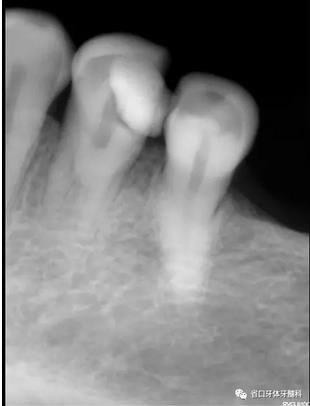

圖1:術(shù)前X線片:34遠(yuǎn)中高密度影及髓,疑似雙根管

1、以單根管為主的下頜第一前磨牙,由于發(fā)育上的特點(diǎn),根管系統(tǒng)存在較大變異,可能是最難以進(jìn)行根管清潔和成型的一組牙齒,常因?yàn)楹雎粤穗p根管及多根管的存在,造成遺漏根管發(fā)生。本病例中,34的術(shù)前X線片可見(jiàn),主根管影像突然消失,提示我們可能存在多根管,CBCT的有助于我們了解根管分叉位置和根管的彎曲情況,全程顯微鏡下治療有助于我們進(jìn)行髓底探查及進(jìn)行有效預(yù)備根充。